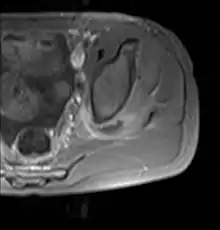

| Transverse T2 magnetic resonance imaging section through the hip region showing abscess collection in a patient with pyomyositis. | |

| Diagnostic method | Diagnostic method used for PM includes ultrasound, CT scan and MRI. Ultrasound can be helpful in showing muscular heterogeneity or a purulent collection but it is not useful during the first stage of the disease. CT scan can confirm the diagnosis before abscesses occur with enlargement of the involved muscles and hypodensity when abscess is present, terogenous attenuation and fluid collection with rim enhancement can be found. MRI is useful to assess PM and determine its localization and extension |